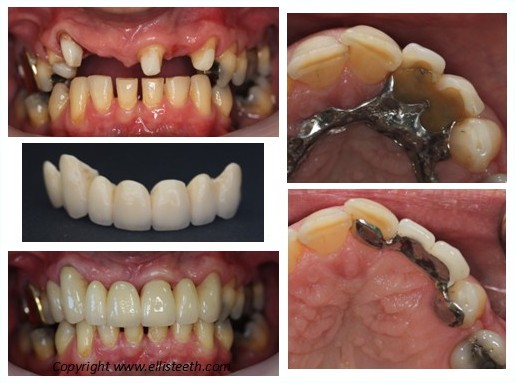

Dentures

Removable Prosthodontics

Dentures can be partial or full and constructed from plastic or metal to fit the gums and/or remaining teeth.

They are bulkier than bridges and implant crowns and tolerance can be an issue. They are less invasive and have many benefits especially when well planned and are easier to maintain.

Dentures should be removed at night and cleaned with a brush and cleaning soak.

Restorative Dentistry is often destructive of tooth structure and will always need enhanced maintenance. Optimising tooth cleaning by the patient and professionally by the dental hygienist is essential. All restorations have a lifespan, also called longevity, and for veneers, crowns, bridges are considered as averages by scientific studies and in the order of 10-12-15 years with many caveats to these figures. The case below shows that sometimes there are different ways to achieve excellent results.